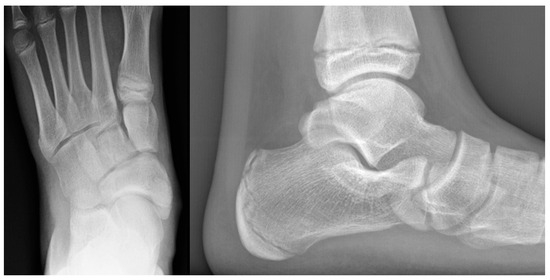

Diagnosis is based on patient history and clinical presentation. In most cases, the clinical presentation alone is adequate to establish the diagnosis, and imaging is not routinely required during the initial stages of the condition. First-line imaging studies include plain radiographs for differential diagnosis; however, they are not diagnostic, as a fragmented calcaneus can also be observed in asymptomatic children (Figure 2). The nucleus, in addition to being fragmented, may also be physiologically thickened, bipartite, smaller, or displaced upwards or downwards, without having any pathological relevance [14]. Diagnosis is further supported by magnetic resonance imaging (MRI), which can demonstrate bone marrow edema, microfractures, and stress-related bone responses [13] (Figure 3 and Figure 4).

Figure 2.

Radiograph of an 8-year-old asymptomatic male patient showing irregularity and fragmentation of the calcaneal apophysis.

Figure 3.

Eleven-year-old male patient. Radiograph (left) demonstrating typical fragmentation and bipartite appearance of the calcaneal apophysis. MRI (right) showing detailed fragmentation with associated bone marrow edema.

Figure 4.

Ten-year-old male patient. Radiograph (left) revealing marked fragmentation, thinning, and bipartition of the calcaneal apophysis. MRI (right) demonstrating extensive associated bone marrow edema.